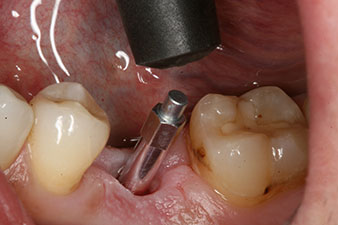

The implant was placed as planned after thorough removal of the granulation tissue (blueSky, bredent).

The torque used for the machine-driven placement was 43 Ncm. In addition, after screwing a measuring post (SmartPeg) specially matched to the implant, the ISQ value was measured with the probe of the W&H Osstell ISQ module.

This module is an optional extra for the W&H Implantmed and is docked to the implantology motor (see Fig. 11). The dimensionless ISQ value immediately after insertion was 64 orovestibular and 68 mesiodistal (maximum value = 100).